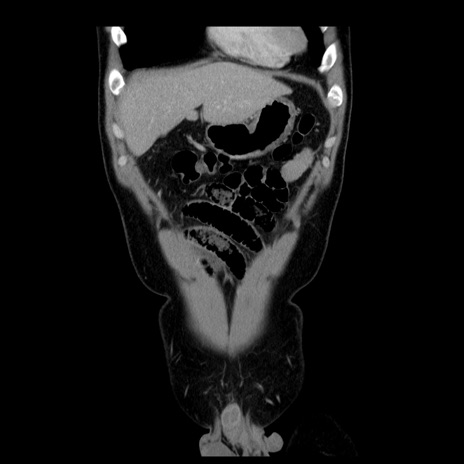

横断像